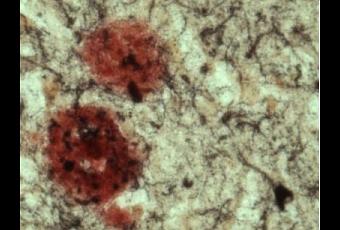

Source: The Journal of Neuroscience 15 August 2012, 32(33):11390-11395; doi:10.1523/JNEUROSCI.0757-12.2012 Alzheimer's β-Secretase (BACE1) Regulates the cAMP/PKA/CREB Pathway Independently of β-Amyloid (Visuel @ Sanford-Burnham Medical Research Institute « Plaques béta-amyloïdes (rouge) dans le cerveau d'un patient atteint de la maladie d'Alzheimer »).